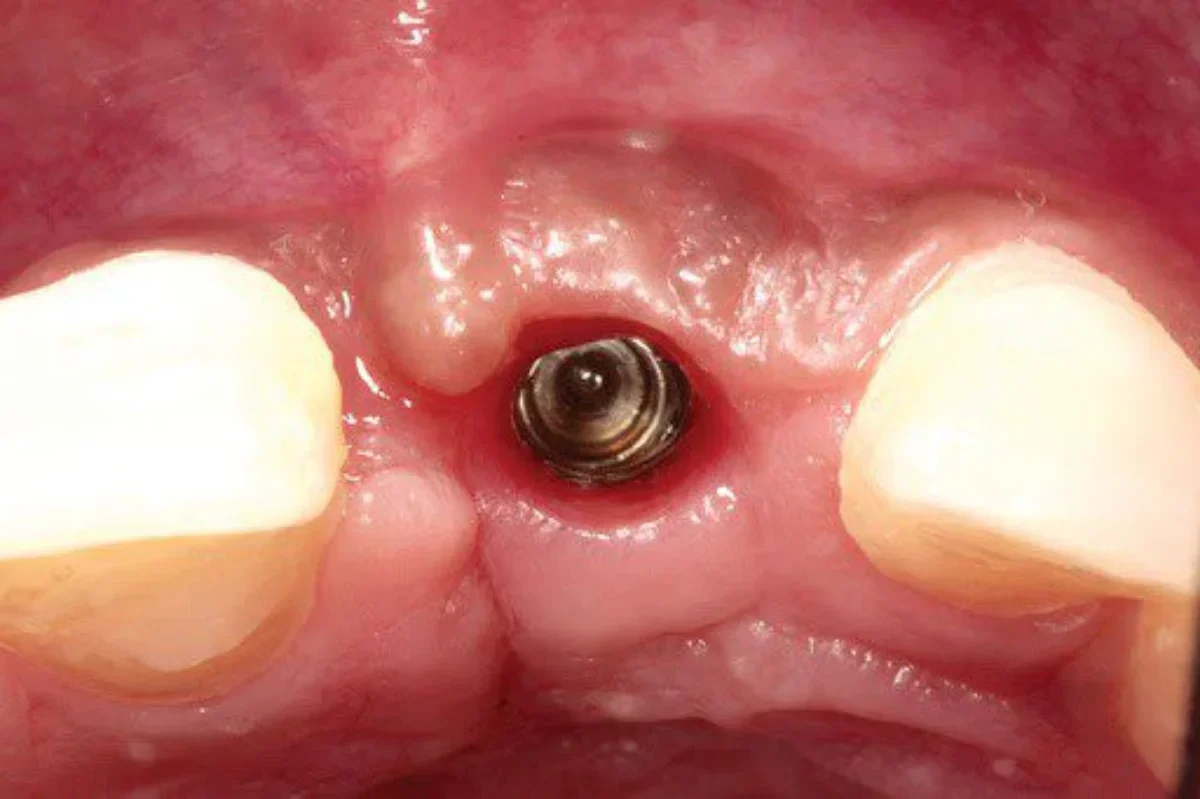

Pentru cei care au pierdut unul sau mai mulţi dinţi, implantul dentar este cea mai sănătoasă şi conservatoare opţiune, graţie modului în care implantul se integrează în os, devenind parte din acesta. Implantul dentar înlocuieşte rădăcina dentară eficient, fiind un suport stabil şi rezistent al coroanei dentare, rezultând un dinte nou, artificial, dar care a […]

Tratamentul de implantologie orală este expresia evoluției spectaculoase a medicinei dentare. Fiind vorba despre o procedură complexă și de durată, este important pentru tine, ca pacient, să cunoști exact etapele acestui tip de tratament modern. 1. Prima consultație Prima consultație este momentul în care medicul ia cunoștință de: ceea ce te deranjează (dureri, dinți afectați sau […]

Dacă vă lipsesc unul sau mai mulți dinți, implanturile dentare sunt soluția pentru dumneavoastră. Implanturile dentare sunt un înlocuitor permanent pentru dinții lipsă, iar acestea arată și se simt la fel ca dinții dvs. naturali. Implanturile dentare se pot pune dupa varsta de 21 ani si sunt cea mai buna solutie. Implanturile dentale pot fi facute […]